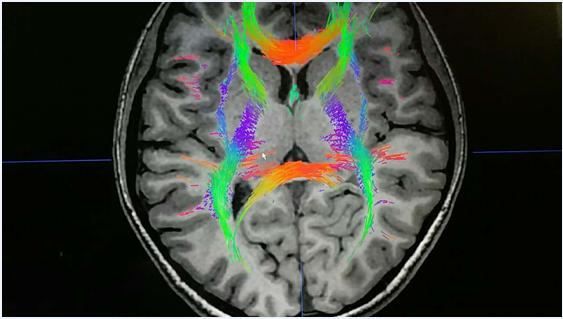

第五代腦立體定向技術(shù)基于情感環(huán)路和遞質(zhì)分泌學(xué)說,首先通過DTI、MRI、CT等影像醫(yī)學(xué)技術(shù)檢查,然后將這些結(jié)果輸入到手術(shù)計(jì)劃系統(tǒng)中,通過手術(shù)計(jì)劃對影像醫(yī)學(xué)數(shù)據(jù)進(jìn)行分析并定位神經(jīng)調(diào)控靶點(diǎn),規(guī)劃手術(shù)路徑和方案,引導(dǎo)手術(shù)醫(yī)師進(jìn)行手術(shù),神經(jīng)調(diào)控靶點(diǎn)定位非常精準(zhǔn),誤差僅不足±0.01mm,正是由于定位精準(zhǔn),因此我們采用的是多靶點(diǎn)神經(jīng)調(diào)控技術(shù),多靶點(diǎn)神經(jīng)調(diào)控可以更有效的幫助患者控制復(fù)雜的精神癥狀。由于采用的是微創(chuàng)技術(shù),因此也不會(huì)像傳統(tǒng)開顱手術(shù)一樣,整個(gè)手術(shù)過程出血量不足10ml,手術(shù)僅需在患者頭部取1-3cm左右的小切口即可完成手術(shù),水腫、感染等風(fēng)險(xiǎn)相較傳統(tǒng)開顱手術(shù)僅不足1%。